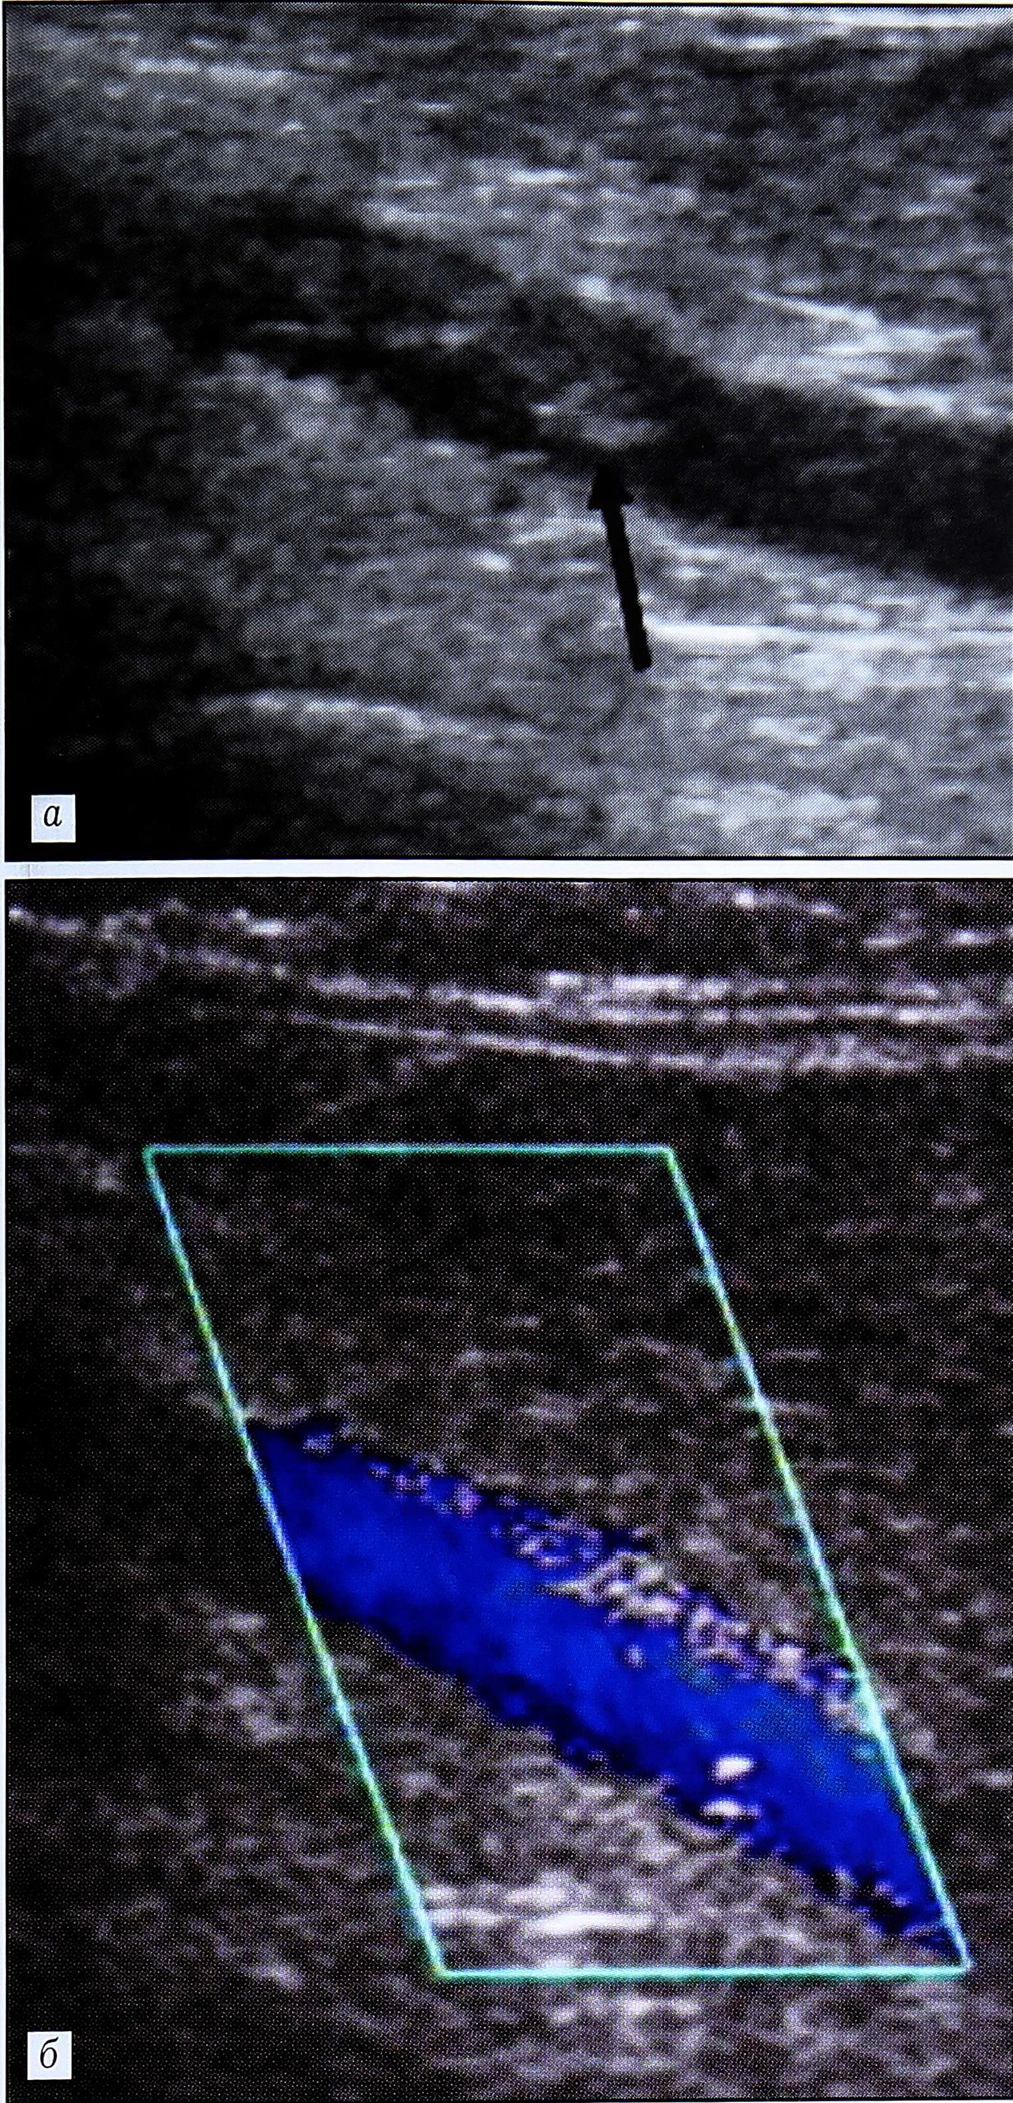

Во всех случаях проксимальный ТГВ был подтвержден ретроградной илиокавальной флебографией. Диагнозы полностью совпали, в том числе и в отношении уровня верхней границы тромба (рис. 2). При подтверждении флотирующего характера тромбов устанавливали постоянный кава-фильтр. Больным с окклюзивными тромбами проводили антикоагулянтную терапию низкомолекулярным гепарином в лечебных дозах. При динамическом наблюдении нарастания тромбоза отмечено не было.

Рис. 2. Ультрасонограмма (а) и ретроградная илиокаваграмма (б) больного с флотирующим тромбом (стрелки) в общей бедренной вене.

Тромбоэмболия легочной артерии развилась у одного из 14 пациентов с выявленным ТГВ (1,4% от общего числа обследованных). Это была больная 77 лет с переломом шейки бедра. Симптомы легочной эмболии появились на 4-е сутки после эндопротезирования тазобедренного сустава. В тот же день при ультразвуковом ангиосканировании выявлен флотирующий ТГВ с проксимальной границей в общей бедренной вене на контралатеральной конечности (рис. 3). Во время ретроградной илиокаваграфии установлен кава-фильтр.

Рис. 3. Ультрасонограмма (а) и флебограмма (б) конечности, контралатеральной по отношению к оперированной: флотирующий тромб в общей бедренной вене (стрелки).